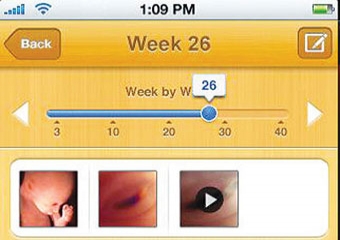

تدور أسئلة كثيرة في ذهن المرأة الحامل وزوجها خلال فترة الحمل، مثل «ما حالة الطفل المفترضة في هذه المرحلة؟»، و«ماذا يجب أن أشعر به؟»، و«كيف شكله الآن؟»، وغيرها. وبإمكان الحامل والمهتمين بالحمل معرفة الكثير من المعلومات عبر برنامج «الحمل وتطور الطفل» Pregnancy & Baby Development المجاني على أجهزة «آي فون» و«آي بود تاتش» و«آي باد» (يتطلب البرنامج نظام التشغيل «آي أو إس 3.0» أو أحدث).

ويمكن للمستخدم إدخال تاريخ الولادة المتوقع، ليعرض البرنامج رسوما بيانية ومقالات تشرح المرحلة التي يمر فيها الجنين حاليا، بالإضافة إلى تخصيص منطقة لكتابة الملاحظات أثناء زيارة الطبيب.

ويمكن مشاهدة شكل الجنين وفقا لكل أسبوع من النمو، وعرض معلومات عن حواسه (مثل تطور حاسة الذوق والخلايا الدهنية)، وما الذي يفترض أن تشعر به المرأة الحامل في تلك المرحلة، مع تقديم نصائح كثيرة حول الأغذية التي ينصح بالابتعاد عنها خلال فترة الحمل (والأسباب وراء ذلك). ويمكن تحميل البرنامج من متجر «آي تونز» الإلكتروني، لتكون تجربة الحمل واضحة للجميع.